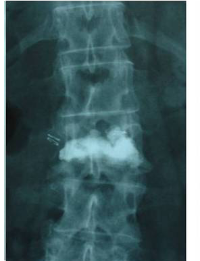

Clinical case example of a lumbar vertebral body resection (corpectomy) and reconstruction of a burst fracture at level L4.

Vertebral body resection (corpectomy) and reconstruction of complex vertebral and burst fractures

Severe vertebral body fractures, i.e. conminute and burst fractures, may require a partial vertebral body resection (corpectomy) and reconstruction with an expandable vertebral body cage. Especially severe fracture cases are also those with a bone fragment moving into the spinal canal that compresses on neural structures, such as the spinal cord and causes spinal canal stenosis. Corpectomy allows to resect most of the fractured body, including the bone fragments pushing on the nerves and intruding into the spinal canal. The vertebral body reconstruction is usually rounded up with a posterior augmented instrumented fusion of the adjacent levels to the fracture. All of this allows a proper healing of the fracture and the patient to recover without pain.